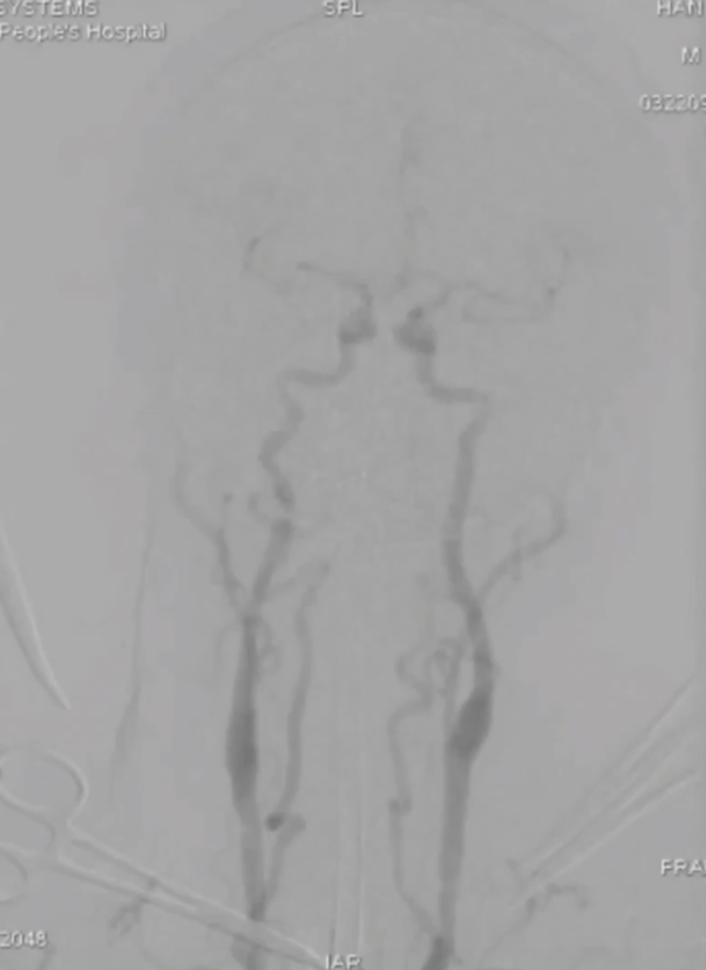

术后造影:主动脉夹层消失,无明显内漏,弓上三分支动脉显影通畅。降主动脉真腔增大,显影通畅,内脏动脉显影良好。颅内动脉显影通畅,未见明显栓塞影像。

波科支架怎么样陆信武:激光原位开窗重建弓上分支治疗A型主动脉夹层_https://www.jmylbn.com_新闻资讯_第9张波科支架怎么样陆信武:激光原位开窗重建弓上分支治疗A型主动脉夹层_https://www.jmylbn.com_新闻资讯_第10张波科支架怎么样陆信武:激光原位开窗重建弓上分支治疗A型主动脉夹层_https://www.jmylbn.com_新闻资讯_第11张

支架植入后:术后12个月随访:复查主动脉CTA可见主动脉重塑良好,弓上三分支显影通畅,无内漏形成。